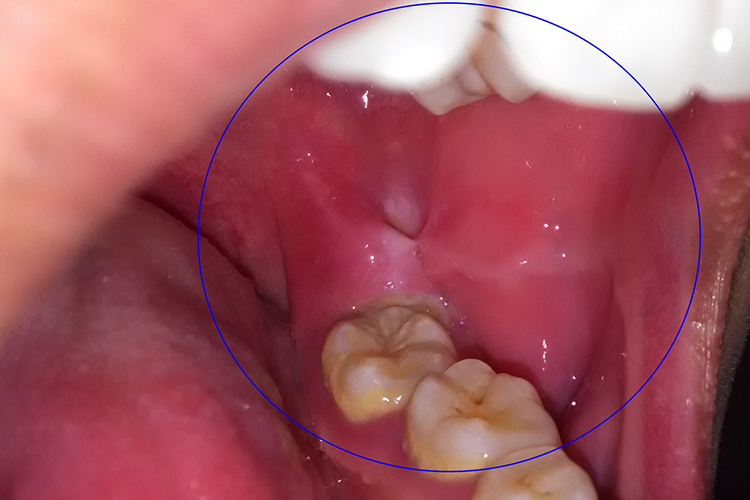

腮腺炎:炎症早期,症状轻微或不明显,腮腺区轻微疼痛、肿大、压痛。导管口轻度水肿、疼痛,从而使口腔两侧颊黏膜水肿。随着疾病的进一步发展,炎症会扩散到腮腺周围组织,伴发蜂窝组织炎。